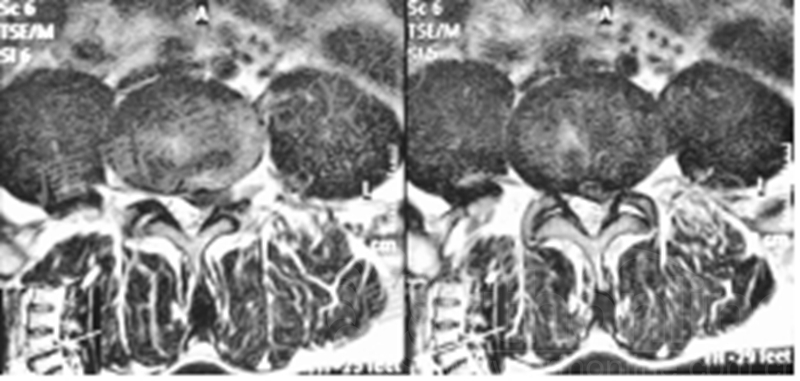

影像学检查:

诊断:腰椎椎间融合术后融合器后移

手术方案:显微镜辅助MI-TLIF腰椎翻修术

术中视频:http://api.orthonline.com.cn/attach/Case3.mp4(术中发现因前次手术全椎板及关节突切除,TLIF的第一步,即关节突关节的定位落脚点难以找到。显微镜下通过Kambin三角解剖位置,进行从外至内的解剖,寻找cage尾端;此外,因大量瘢痕渗血,难以进行充分止血;但在显微镜的照明和放大视野下,操作均可在不伤及神经的前提下进行。由于终板骨质吸收,椎间隙塌陷,导致术野内可同时看到出行根和走行根。而在显微镜下,能够通过调整景深和视线角度,精准充分处理椎间隙骨性终板。无手术并发症)